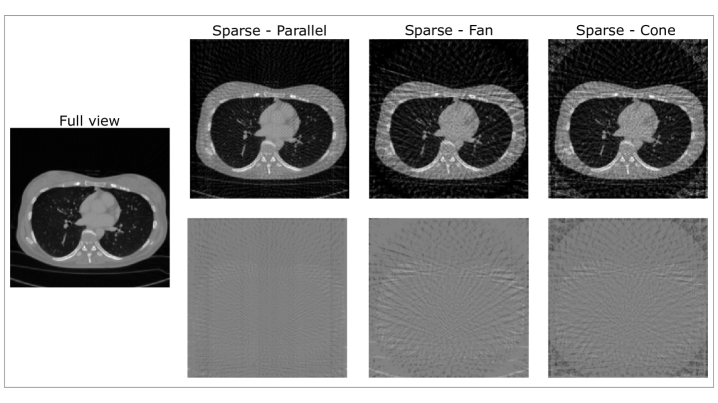

For all beam geometries, a source-to-object distance of 570 mm and a source-to-detector distance of 1040 mm were used in accordance with the geometry of the clinical CT systems as reported in the corresponding DICOM files. Fig. 1 depicts an example axial slice sparsely-sampled with 64 views for all beam geometries, in comparison to the full-view reconstruction.